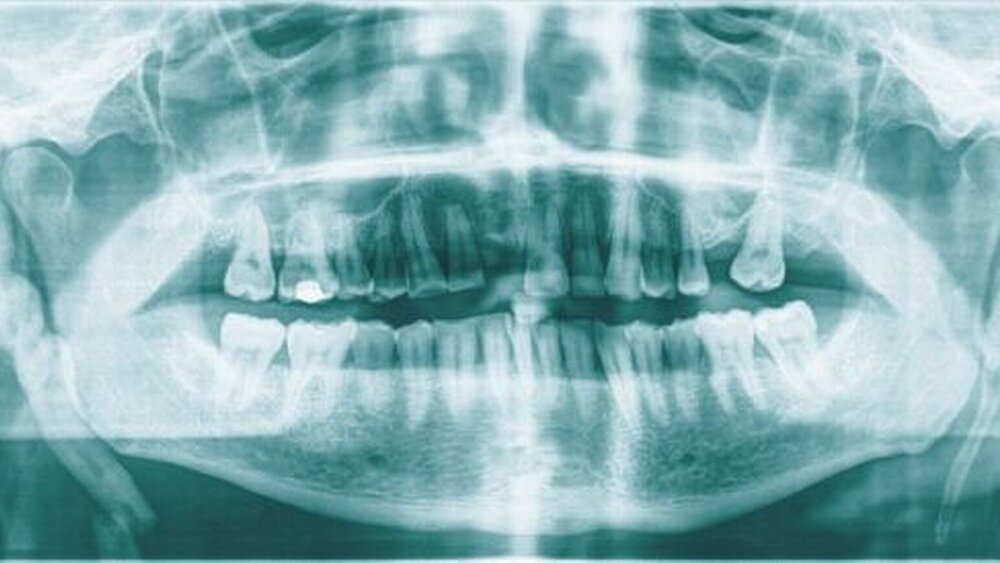

Zur bildgebenden Diagnostik erfolgte die Darstellung des Viscerocraniums mittels digitaler Volumentomografie. Hier zeigten sich sehr ausgedehnte Megastyloides beidseits mit der typischen Lagebeziehung zum Os hyoideum (Abbildung 1).

Relevant für die zahnärztliche Praxis ist das Eagle-Syndrom als seltene, klinisch schwer differenzierbare Schmerzursache, das aber in der einfachen Panorama-Schichtaufnahme in der Regel bereits als Blickdiagnose erfassbar ist.

• Das Eagle-Syndrom ist eine seltene Schmerzursache, ist aber in der Regel als Blickdiagnose im Orthopantomogramm erkennbar.